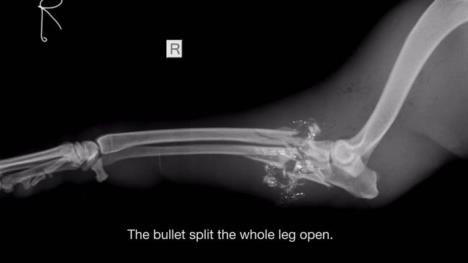

Metak je rascepao celu njenu nogu.